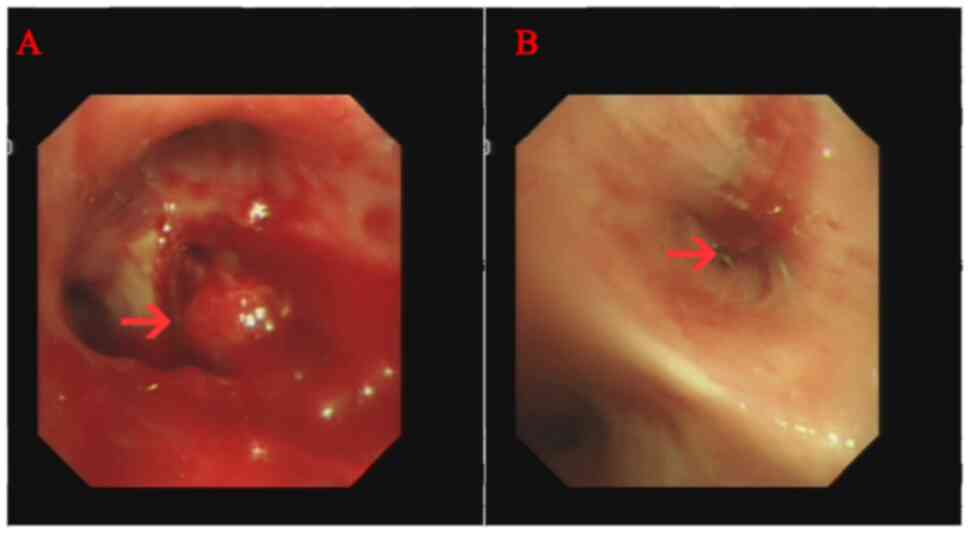

Sudden hemoptysis occurred in November 2020 and a new obstruction in the lumen was noted following bronchoscopy (Fig. 3). Pathological examination of brush cytology smear under a microscope demonstrated SCLC (Fig. 4). Immunohistochemistry was negative for CK7 and positive for pancytokeratin (PCK), chromogranin A) and SyN(Synaptophysin). A marked decrease in foreign body count was observed after combining chemoradiotherapy with osimertinib treatment through chest CT (data not shown). A timeline of the three types of cancer diagnosed is presented in Table IV. No metastases in the skull, bones or gastrointestinal area were observed during treatment. In August 2022, the patient succumbed to progressive lung cancer and no autopsy was performed.

Figure 3.

Bronchoscopic findings at time of diagnosis of small cell lung cancer. (A) Polypoid endobronchial mass (red arrow) blocked the right upper lobe bronchus (red arrow). (B) Tracheal occlusion after resection of the right lower lobe bronchus.